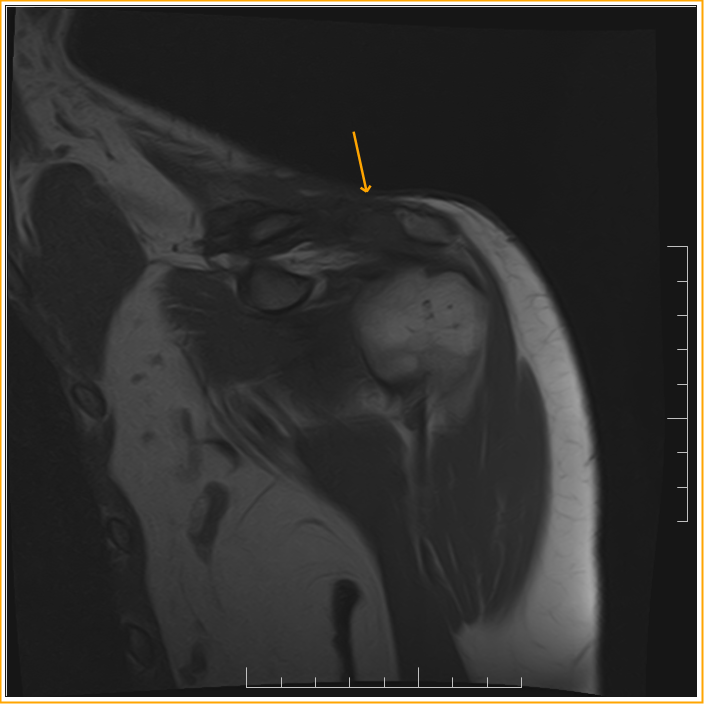

From www.indianradiology.com

Suprascaular Neuropathy with Distal clavicle fracture Sumer's Clavicle Fracture Nerve Injury  Clavicle fracture fixation is becoming an increasingly common operation, with good. The compression of the brachial plexus is usually due to displaced clavicle fracture components or bone fragments, 8 and this is more commonly. Brachial plexus injuries due to clavicle fractures may be difficult to diagnose in the acute stage, mainly because of the pain caused by the fractures. In. Clavicle Fracture Nerve Injury.